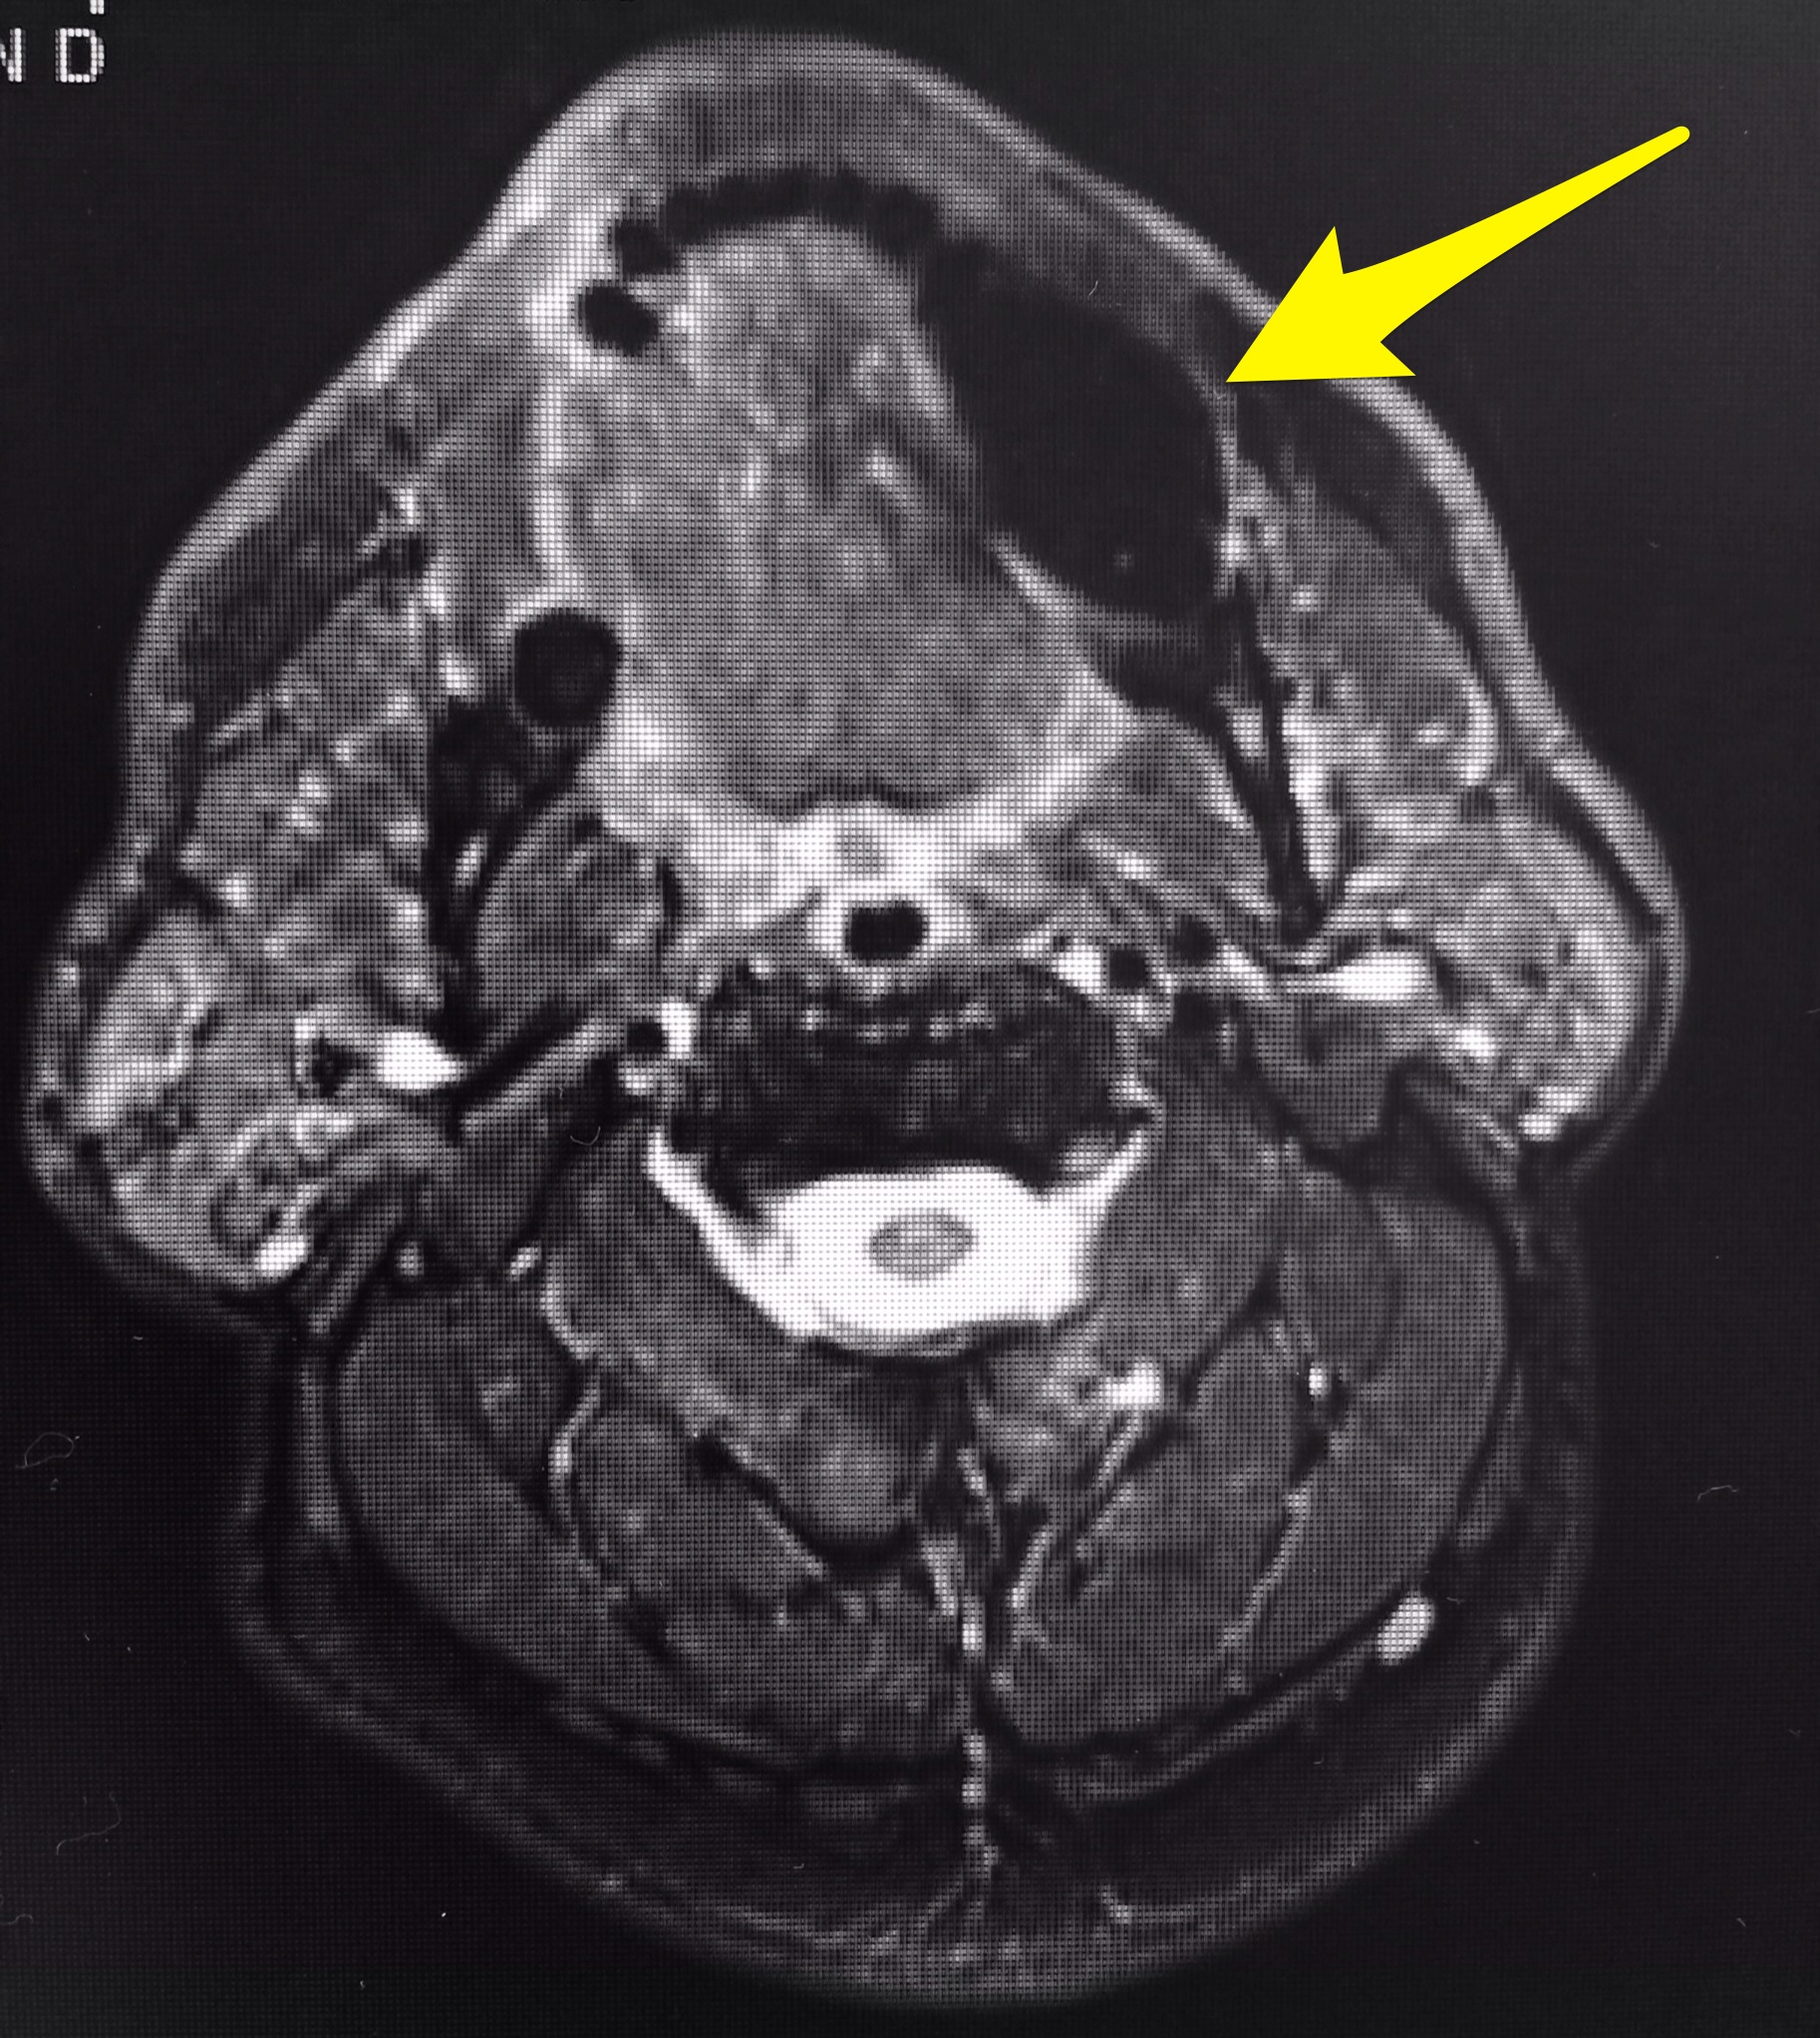

Quadrigeminal plate cistern lipoma. MRI demonstrates a mass in the …

📃 Lipoma of the corpus callosum

Lipoma of Corpus Callosum – Stock Image – C043/0175 – Science Photo Library

Intracranial Lipoma | The Neurosurgical Atlas